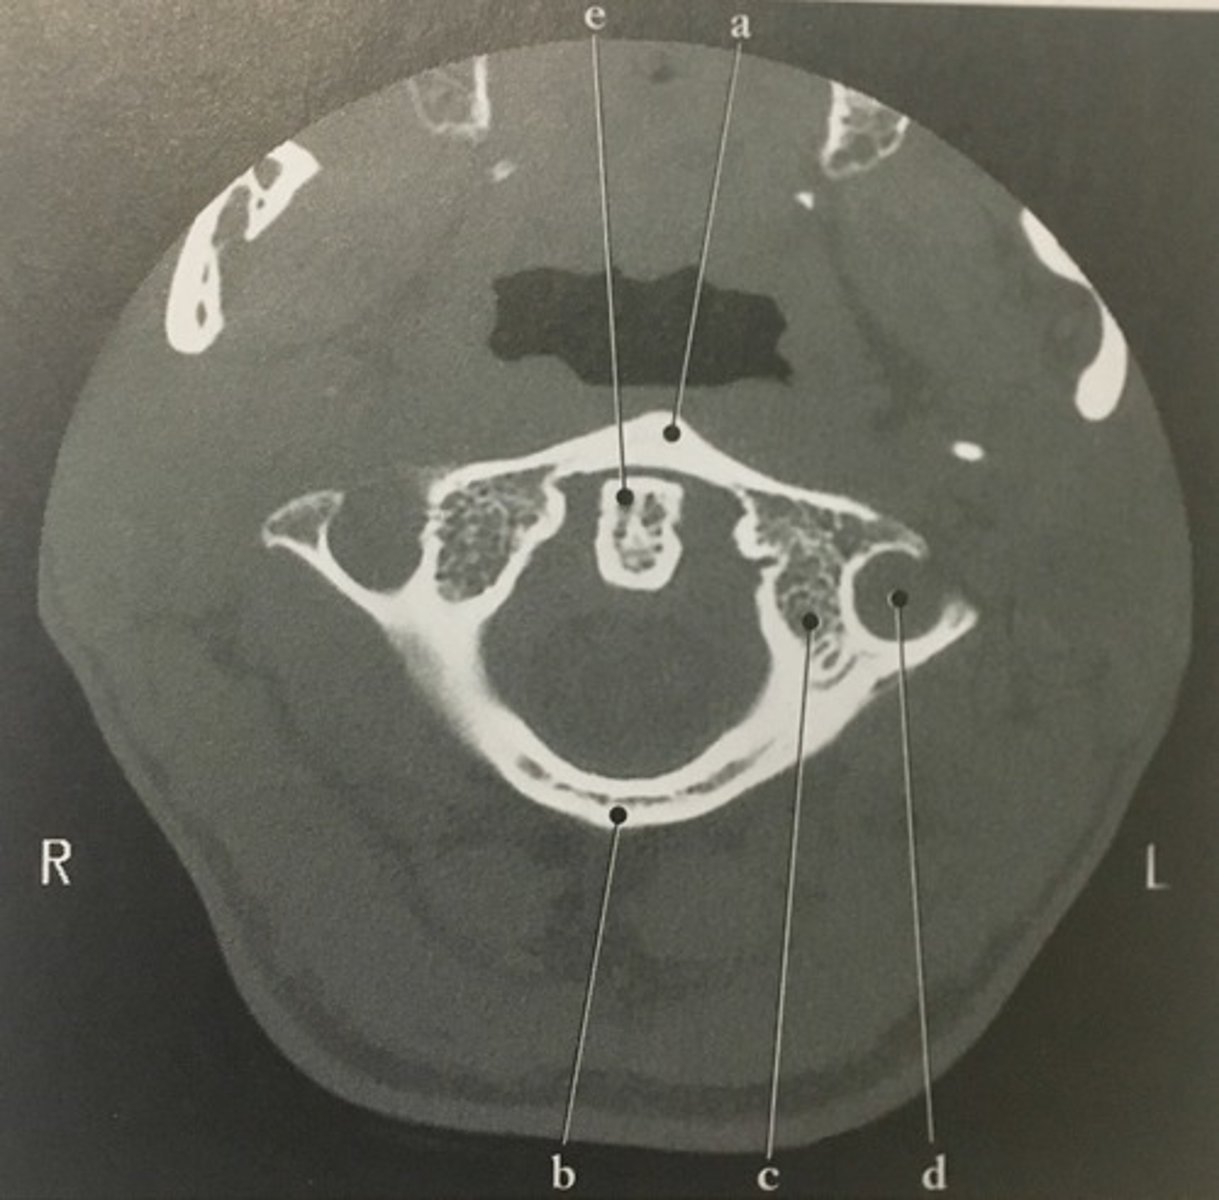

Identify structure A on this axial CT slice of the C1.

<p>Identify structure A on this axial CT slice of the C1.</p>

Posterior arch

Identify structure B on this axial CT slice of the C1.

New cards

Lateral mass

Semicircular Canal

Number 2 corresponds to which of the following?

Number 4 corresponds to which of the following?